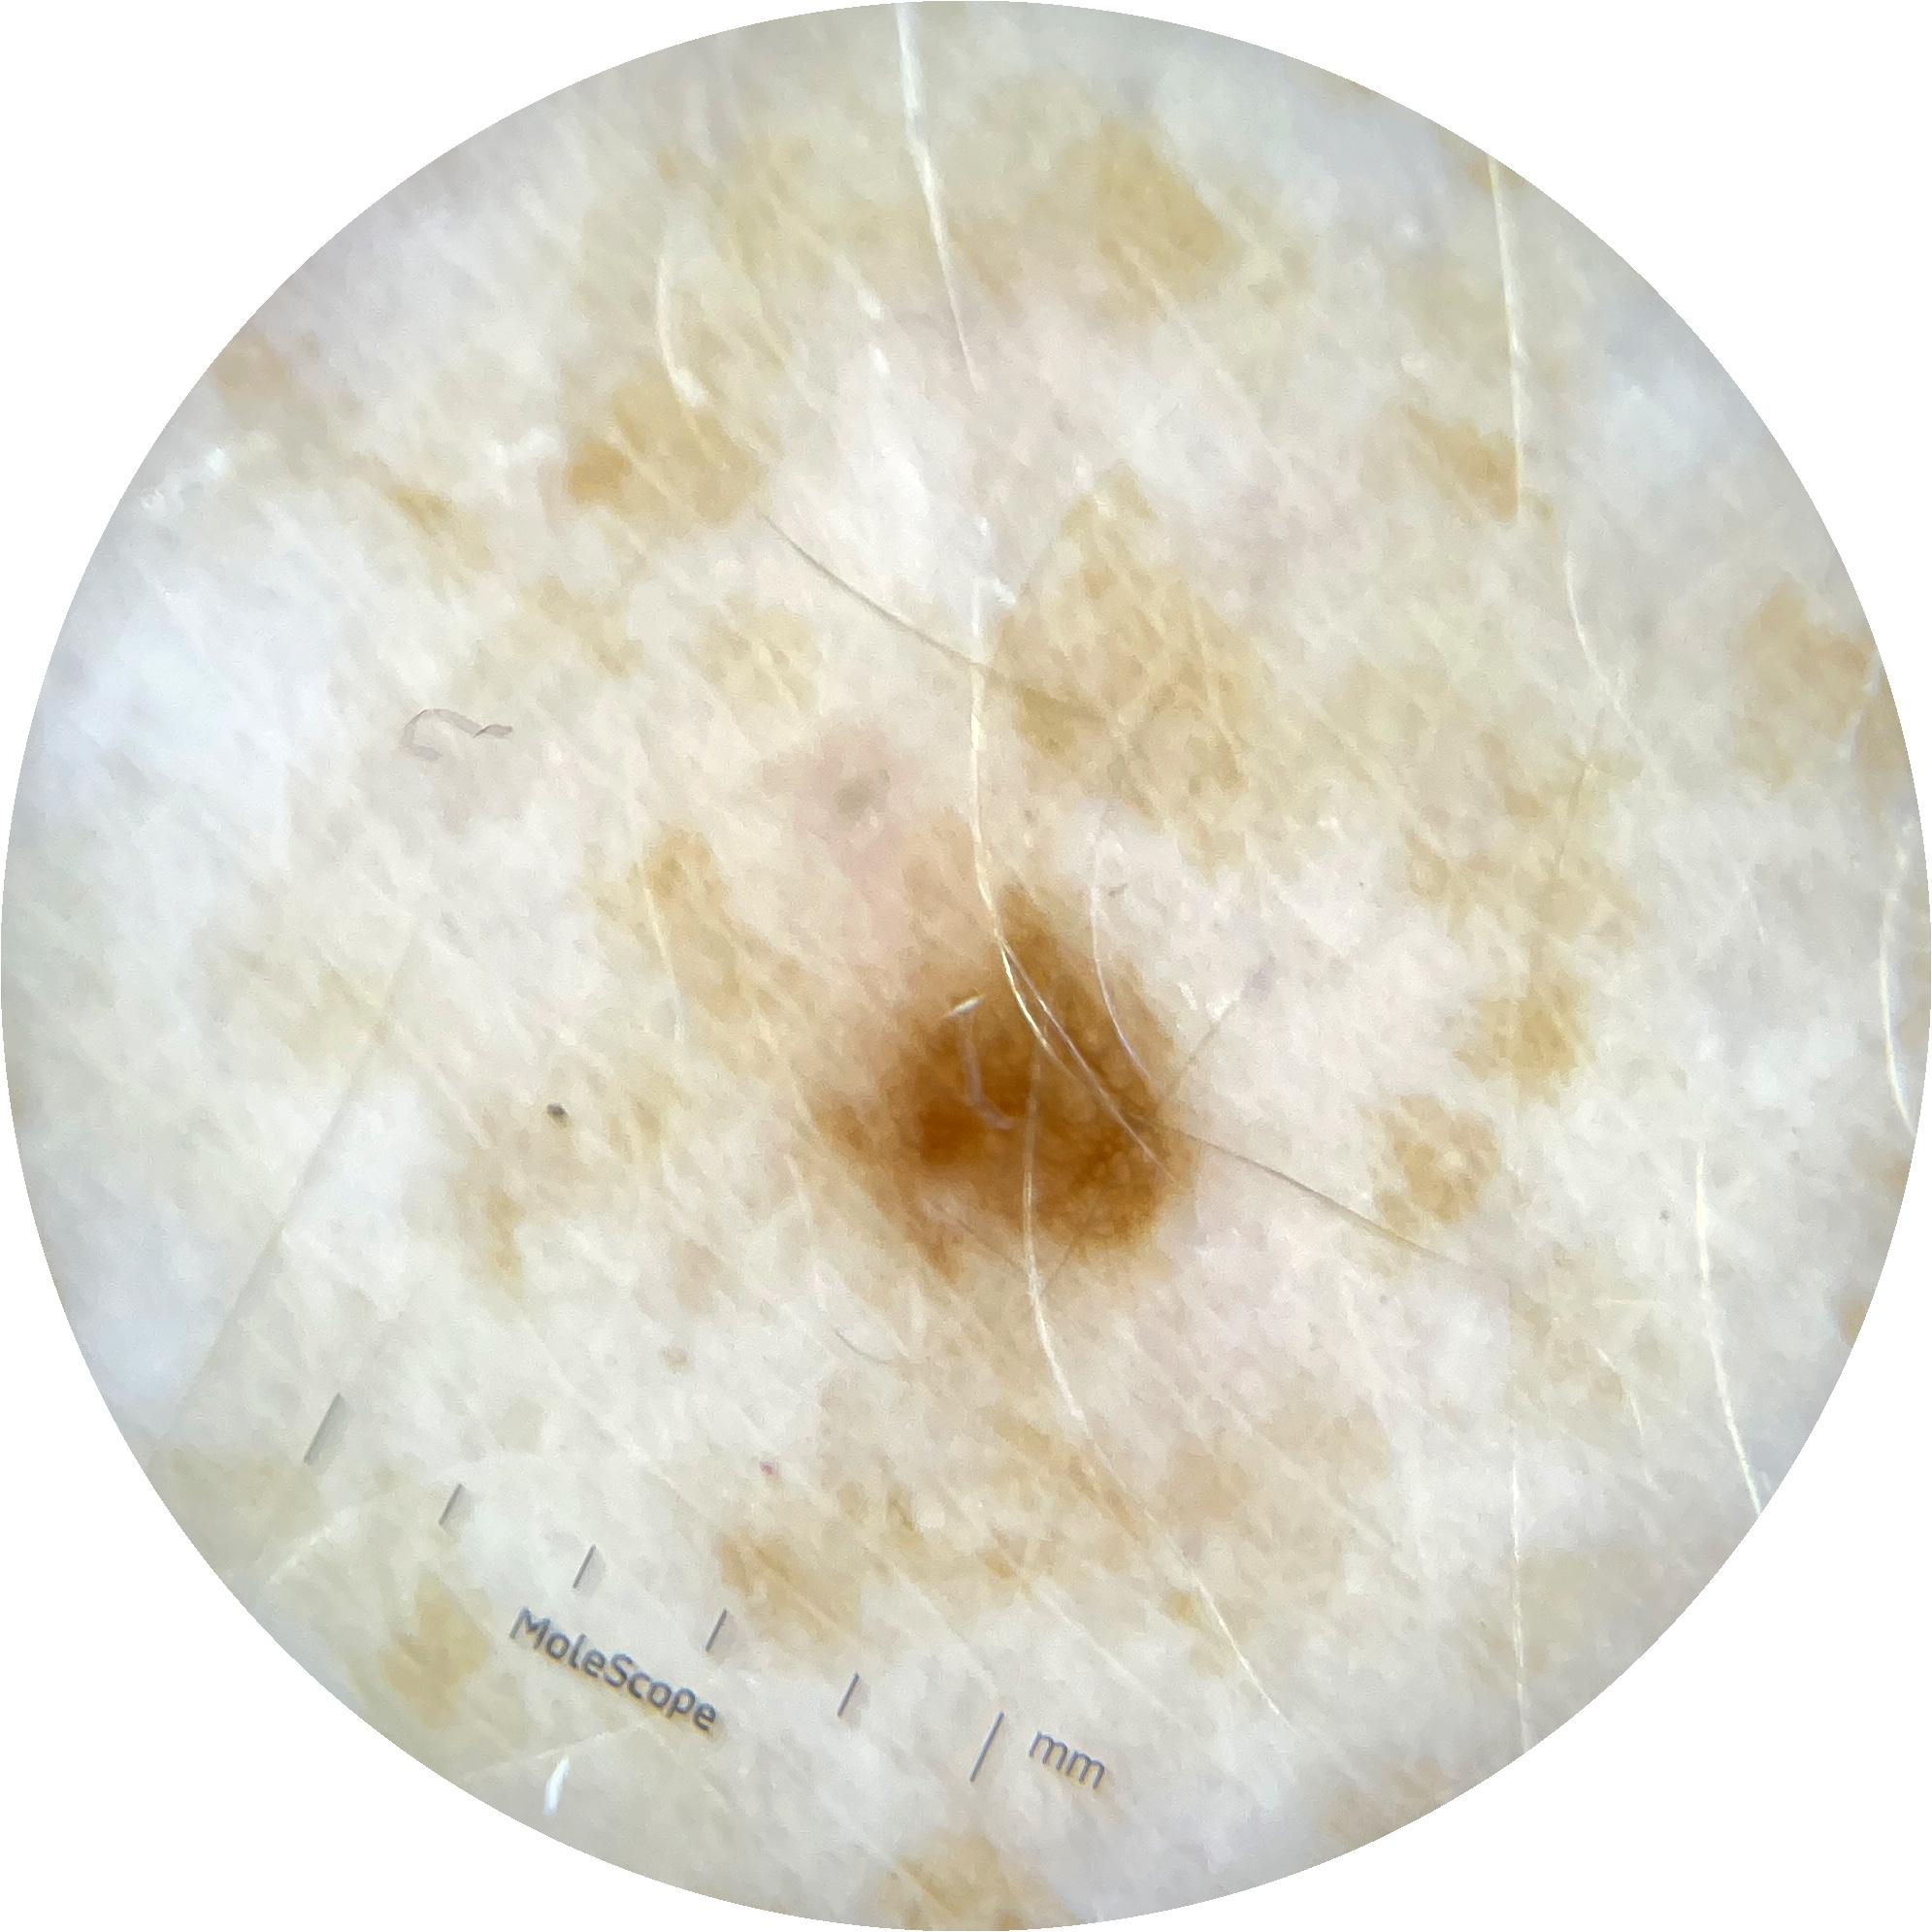

Clinical

Field Value

acquisition_day 148

age_approx 45

anatom_site_1 Head and neck

anatom_site_general head/neck

concomitant_biopsy False

diagnosis_1 Benign

diagnosis_confirm_type single image expert consensus

family_hx_mm True

image_manipulation instrument only

image_type dermoscopic

lesion_id IL_0236417

patient_id IP_8456088

personal_hx_mm True

sex female